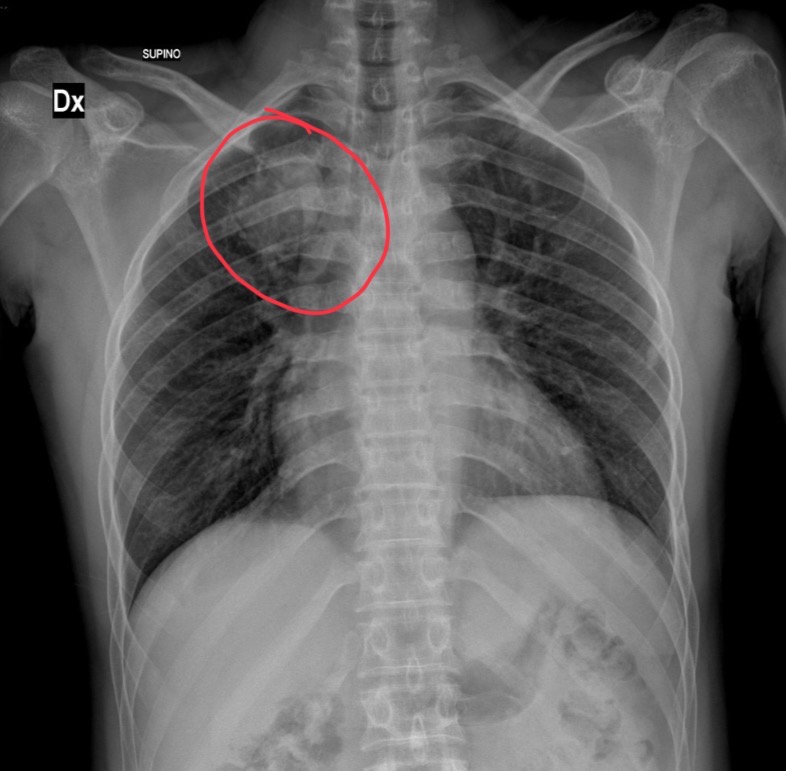

55-year-old male is a smoker presents with chest pain. Fever and cough. Clinicians are worried about seeing cancer on a chest x-ray.

Opacity on xray, air bronchogram needed next

What does this air bronchogram indicate for the pt

Solid upper left lobe “hepatization”. Pt has lobar PNA